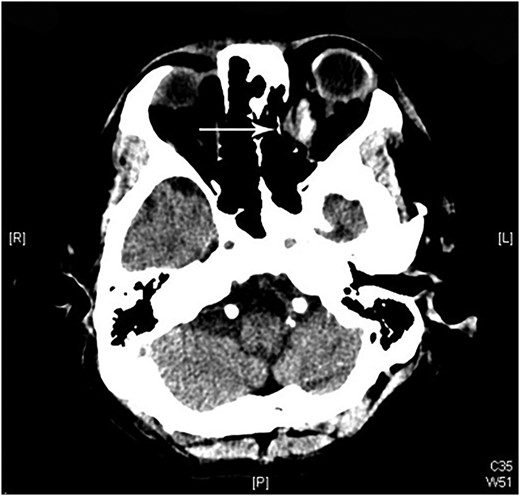

A 60-year-old man was admitted to our medical ward due to aspiration pneumonia. He had a medical history of diabetes mellitus, end-stage renal disease; a tuberculosis bacilli-related thoracic spine infection with paraplegia, and a previous coronary artery bypass graft. During his third day at the hospital, he obtained a ballpoint pen and inserted it into his left eye. On physical examination, the patient appeared to be alert with normal vital signs. The ballpoint pen protruded from his left upper eyelid; it was firmly lodged in his left medial orbit between the globe and nose, causing left eye proptosis (Fig. 1). Neurologic examinations revealed that the patient was neurologically intact except for complete left ophthalmoplegia. Brain CT scanning revealed a tubular foreign body that was located in the anteroposterior plane extending from the orbital apex and directly into the parasellar region (Fig. 2). The metallic portion of the foreign body was entrapped in left optic canal (Fig. 3). There was no evidence of intracranial hemorrhaging or a rupture in the globe (Fig. 4). The patient was treated with high-dose steroids to protect the optic nerve. The plastic ballpoint pen and metallic tip was withdrawn from the orbit smoothly at bedside, and no craniotomy was required. The ballpoint pen had been inserted to an estimated depth of 7 cm through the eyelid and into the orbit. The patient was then transferred to the ICU for close neuro-observation. We initiated intravenous broad-spectrum antimicrobials and vancomycin therapy and continued these medications for three weeks. A psychiatrist was consulted for a complete psychiatric evaluation and suicide prevention. The follow-up CT scan showed no retained foreign bodies or intracranial hemorrhaging (Fig. 5). At the last follow-up examination 2 months after the injury, the patient presented with complete left ophthalmoplegia and blepharoptosis but intact visual function.

The ballpoint pen tip reaches into the parasellar region via the optic canal.